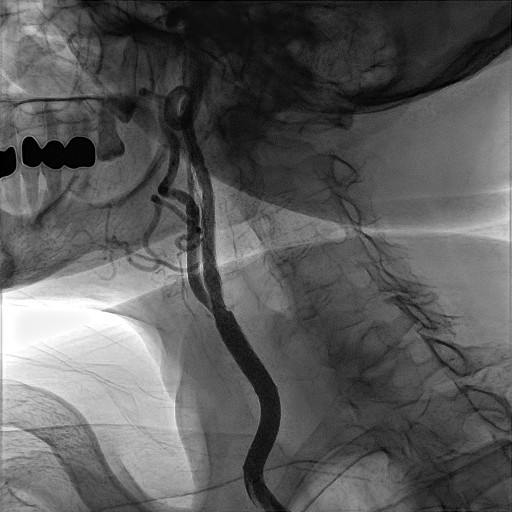

CORONAROGRAFIA

La Coronarografia è l’esame piu’ approfondito per valutare la presenza di restringimenti (“stenosi”) a carico delle arterie coronarie, ovvero delle arterie che nutrono il cuore. Viene effettuata tramite utilizzo di appositi cateteri che vengono inseriti attraverso l'arteria radiale o femorale. Per acquisire le immagini viene utilizzato un liquido chiamato “mezzo di contrasto” che opacizza il lume delle arterie mescolandosi al sangue. Le immagini vengono acquisite da un macchinario che emette una debole radiazione e registra le immagini.